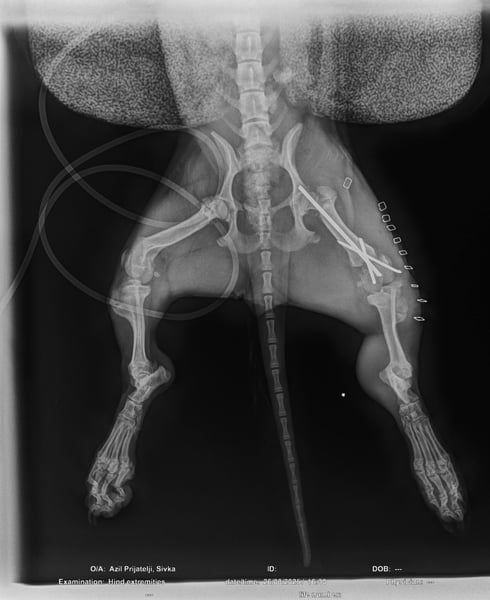

Ilse hatte einmal eine Besitzerin, doch ihr Leben war nicht leicht. Als sie aus dem Hof entkam, wurde sie von einem Auto angefahren und brach sich ein Bein. Zum Glück konnte sie operiert werden – die OP war erfolgreich, und Ilse läuft und rennt wieder ganz normal! Die Metallstifte werden in Kürze entfernt.